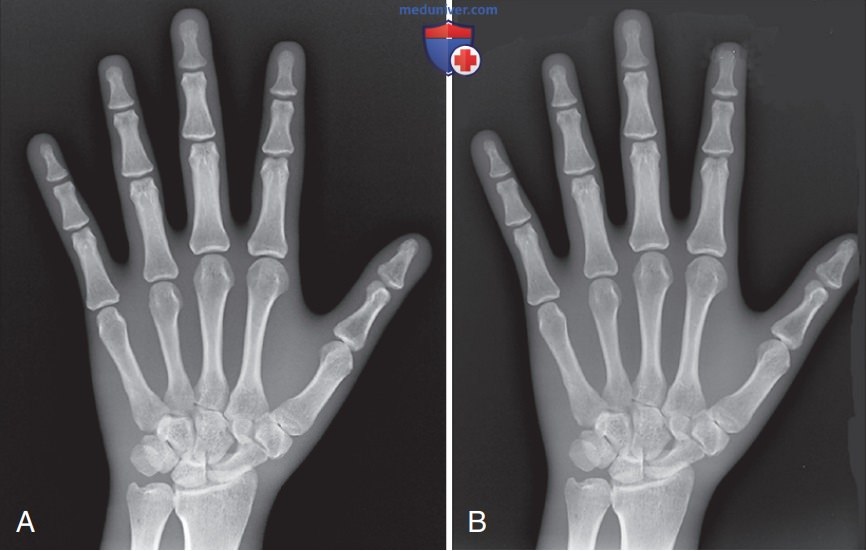

Пространственное разрешение рентгенограммы при оценке ее качества

Рисунок 3. Влияние небольшого (А) и большого (Б) фокусного пятна на детализацию рентгенограммы кисти в ЗП проекции. Сравните трабекулярный рисунок и кортикальный контур. Обратите внимание, как использование небольшого фокусного пятна увеличивает пространственное разрешение.